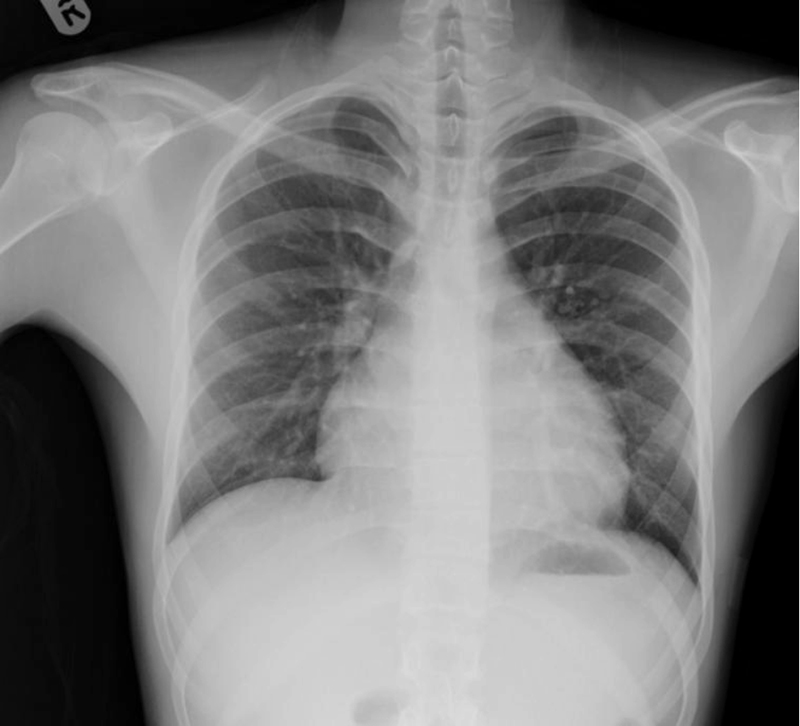

Figure 1: Chest x-ray showing globular cardiac silhouette

Figure 1: Chest x-ray showing globular cardiac silhouette(click to enlarge)

The consultant was struck by the fact that the patient’s heart rate was 110 when lying still in bed and that this increased to 130 when he attempted to sit up. His blood pressure was normal, he looked well, did not appear to have any risks for a pulmonary embolism or an obvious explanation for his tachycardia and markedly elevated D-dimers. His chest X-ray showed clear lung field but he had a rather globular ‘water bottle-shaped’ cardiac silhouette. The ECG revealed widespread T-wave inversion in all leads